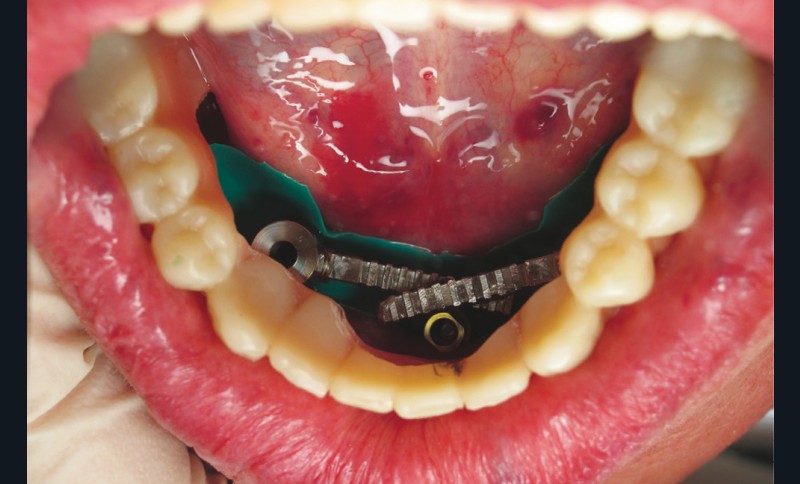

La phase chirurgicale démarre avec une levée de lambeau puis une régularisation crestale afin d’offrir un « large » plateau osseux. Les forages sont assurés par le guide de première intention suivi des différents guides de la trousse Trefoil (fig. 4). Un premier essai est concrétisé : la barre est vissée puis la prothèse est insérée pour contrôle d’absences de contraintes entre les parties. Des meulages sélectifs sont possibles.